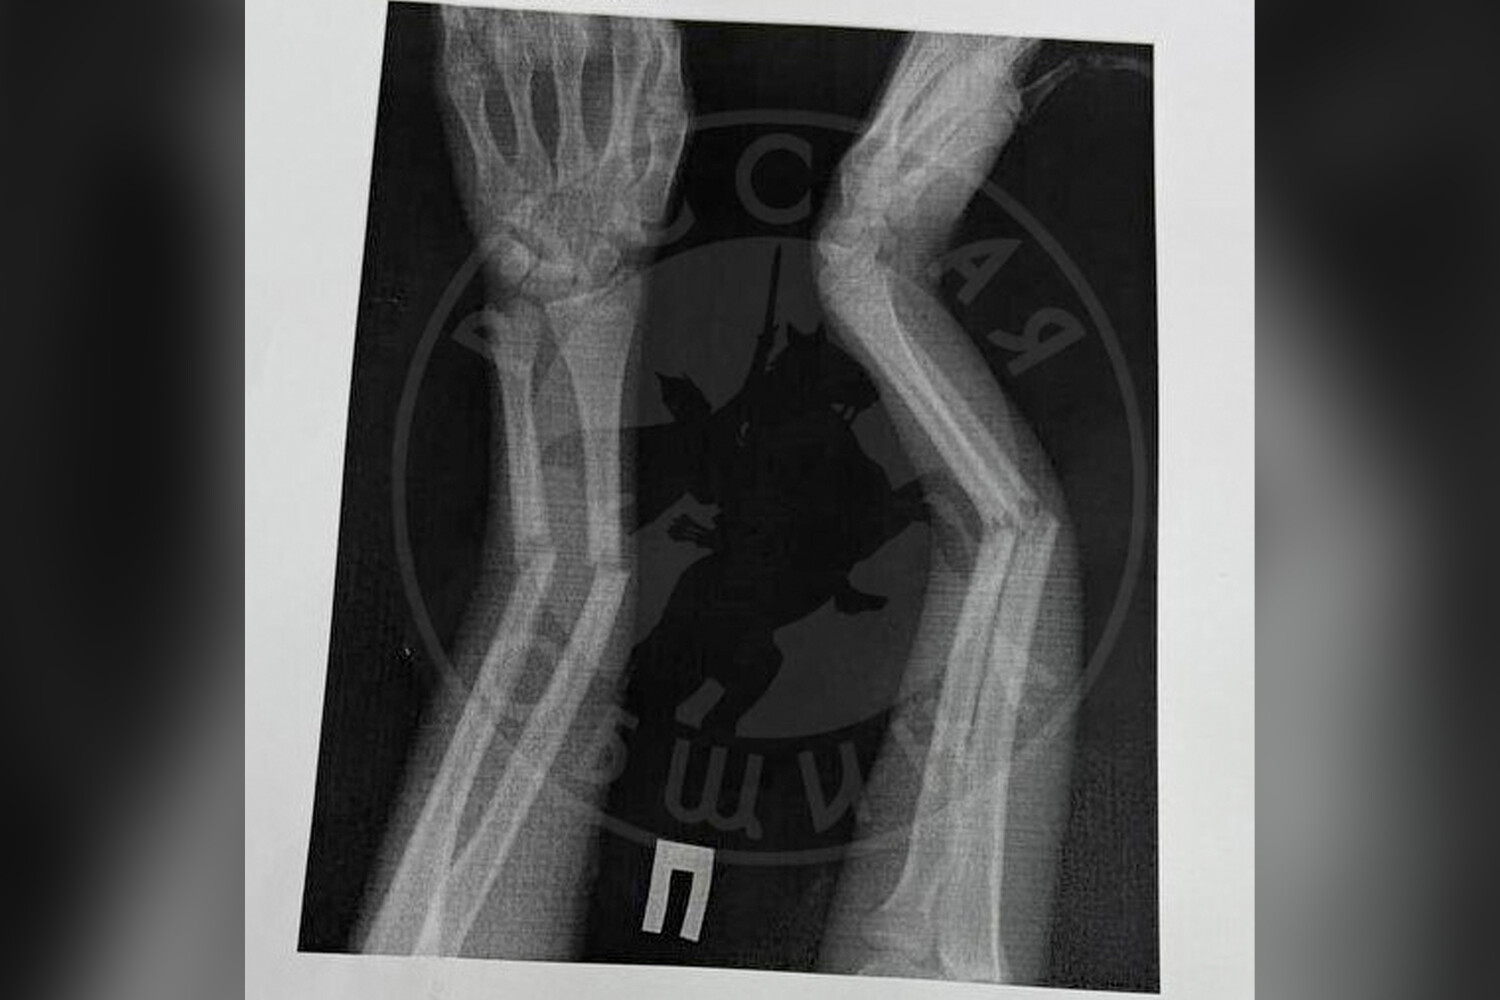

Инцидент произошел в школе №6. По информации издания, мальчик перекинул девочку через плечо и повалил на пол. В результате пострадавшая получила закрытый перелом костей правой руки со смещением. Первую помощь ей оказала школьная медсестра, затем девочку госпитализировали в медицинское учреждение.